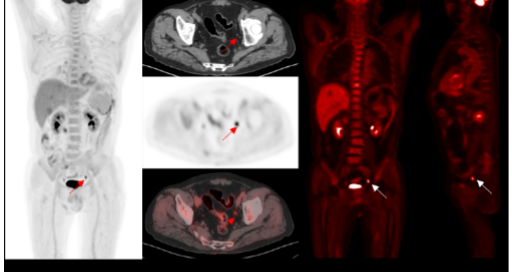

0.05mCi/kg FDG Imaging

2.2mm small Lesion detection